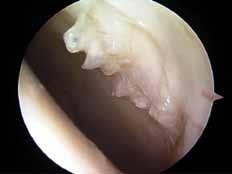

Fråga 2012-6 5p

Kvinna 57 årig tidigare frisk kvinna som inte tidigare har haft några problem med sina knäleder. En dag under vårens trädgårdsarbete känt smärtor i vänster knäled. Söker efter några dagar som jourfall då smärtorna snarast tenderar att öka. I status finner du lätt hydrops. Lätt rörelseinskränkning vänster jämfört med höger knäled. Lätt till måttlig ömhet medialt. Normal SR och CRP.

a. Differentialdiagnoser? (1p)

b. Hur handlägger Du patienten vid detta besök? (2p)

c. Hur utreder man ytterligare om patienten återkommer pga tilltagande besvär efter ett par veckor? (2p)

a. Troliga diagnoser är degenerativ meniskruptur/artros, spontan knäledsosteonekros eller insufficiensfraktur.

b. Noggrant knä- och höftstatus eventuellt slätröntgen och patientinformation om möjliga diagnoser. Smärtlindring och aktivitetsråd.

c. Vidare utredning med MR kan vara

indicerad speciellt för att kartlägga en eventuell osteonekros. Tc-scintigrafi kan också leda till rätt diagnos.